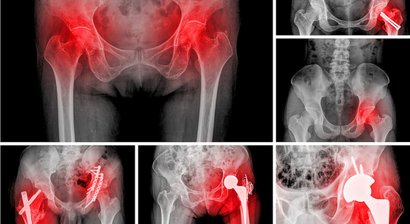

Hüftprothese

Eine Hüftprothese ersetzt ein geschädigtes Hüftgelenk. Neben Knieprothesen zählen Hüftprothesen zu den am häufigsten implantierten Prothesen im Bereich der orthopädischen Chirurgie, die häufigste Indikation für den Ersatz des Hüftgelenks ist die fortgeschrittene Hüftarthrose (Coxarthrose).   Al...